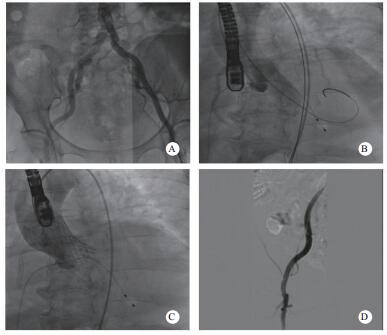

(2)血管造影明确双侧髂股动脉入路情况,选择条件更好的一侧进行手术本病例通过超声引导下穿刺左侧股动脉,但J型导丝难以通过股左侧髂总动脉,提示血管可能存在严重狭窄。随后的造影可见双侧髂总动脉均有不同程度的病变,右侧相对较好(图 2A),故选择右侧作为主入路进行手术。超声引导下穿刺右侧股动脉,置入19 F大鞘内芯,通过有阻力,考虑血管条件差,放弃置入19 F鞘。因瓣膜输送系统的外径与16 F大鞘外径相当,采用无鞘植入的方案,改成16 F cook鞘置入,顺利通过。

| A:外周血管造影;B: 20×40 mm Z-Med球囊行Balloon Sizing;C:植入26 mm Venus-A瓣膜后复查造影;D:复查外周血管入路造影 图 2 患者造影 |

明确冠状动脉情况:该患者有右冠PCI手术史,合并高血压和糖尿病,可能存在需要处理的冠脉病变,所以在置入大鞘后对该患者进行冠脉造影检查,结果提示右冠支架通畅,前降支及回旋支轻-中度狭窄,无需干预处理。

(2)选择合适大小的球囊进行Balloon Sizing测量:在明确上述情况后,还需要选择合适的球囊进行Balloon Sizing测量,同时观察冠脉血流情况进一步评估瓣膜释放后可能出现的冠脉堵塞情况。因术中基于超声测得的瓣环内径为2.11 cm,故选择20 mm×40 mm Z-Med球囊进行测量,在球囊膨胀到最大程度时,可以看到球囊两侧仍存在少量反流,且无明显腰征,左冠及右冠血流通畅(图 2B)。

选择合适大小的瓣膜植入并评估;根据超声和球囊测量的结果,针对该患者,最终选择26 mm Venus-A瓣膜进行手术,植入位置理想,几乎无瓣周漏和跨瓣压差,冠脉血流未受影响(图 2C),复查外周血管造影提示未见明显狭窄及出血(图 2D)。